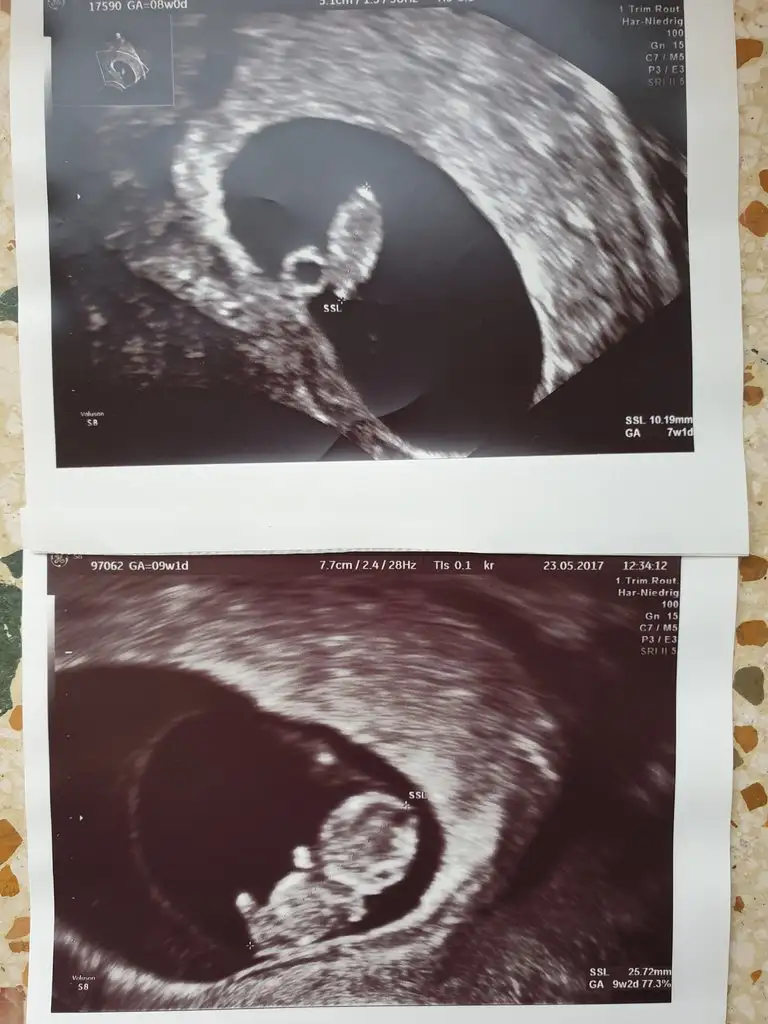

Malesef bilemiyorum cnm bu kese olayında vajinal ultrason yada karından ultrasona göre yorumlaniyor ya gecmise dönük oldugu icin hic hatirlayamiyorum o haftalardaki ultrasonum nasildi.Bazilari ultrason resimlerini ayirt edebiliyor kiyaslamak isteyen olursa atabilirim buraya.Üstteki oglum alttaki bebek seklinde olanda kizim cnm.Rabbim hepimizin gönlündekini nasip etsin insallah💖💖💖